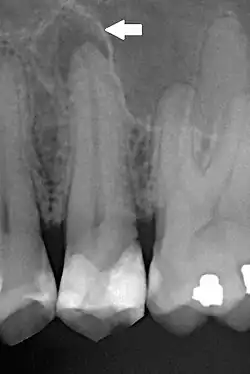

Aspectos radiográficos

A PA pode inicialmente não apresentar nenhum aspecto radiográfico, apenas sintomatologia clínica, em sua fase mais inicial.[1][2] Posteriormente, pode evoluir para apresentar espaçamento do espaço do ligamento periodontal.[1][2] A PA crônica tende a se apresentar como uma rarefação óssea difusa associada ao dente afetado, com perda da continuidade da lâmina dura.[1]